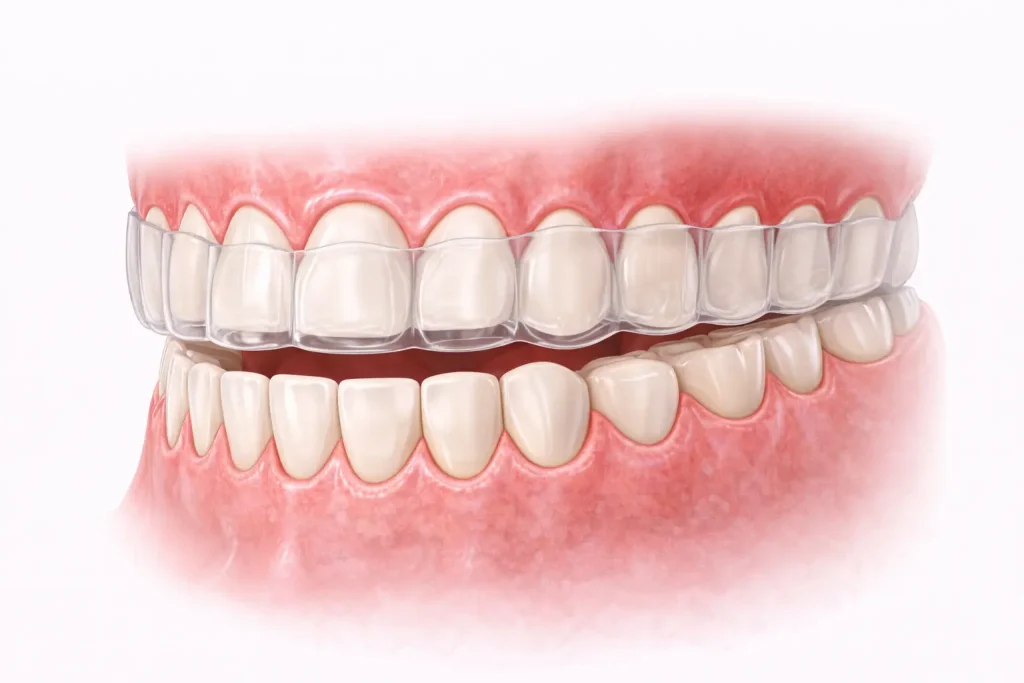

そのため、歯ぎしりや食いしばりの癖がある方は注意が必要です。

前述した通り、起きている間よりも、睡眠時や何かに集中している無意識のうちに強い力が歯にかかることが多いことがわかっており、そのような時に歯や被せ物に大きな負担がかかることがあります。

このような場合には、就寝時にナイトガード(マウスピース)を装着することで歯にかかる力を分散させ、歯を守ることが期待できます。